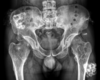

Espondilite anquilosante

Homens jovens, 3 década

Sacroileíte bilateral e simétrica

Coluna: Shiny corners (romanus): erosões nos cantos vertebrais com esclerose reativa;

vértebra quadrada (perda da concavidade anterior); espondilodiscite não infecciosa (lesão de andersson); aparência em bambu (anquilose dos sindesmófitos); sinal da faca (ossificação central - ligamento interespinhoso no rx ap),